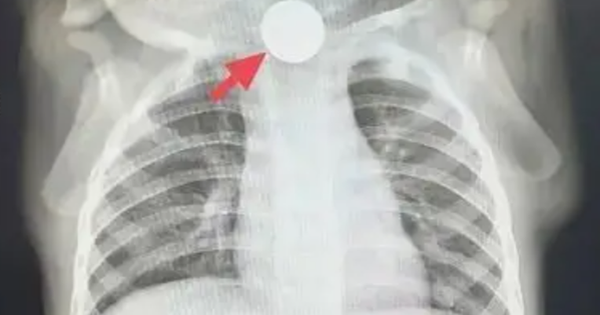

Bé trai 1 tuổi bỏ ăn cả tuần, nguyên nhân được phát hiện khiến bà nội phải thốt lên: "Đúng là lỗi của tôi"

Một bé 1 tuổi bỗng nhiên thay đổi tính nết, chán ăn suốt một tuần! Sau khi được bác sĩ ở Thượng Hải thăm khám, nguyên nhân được phát hiện khiến bà nội nhận ra là sơ suất của mình.